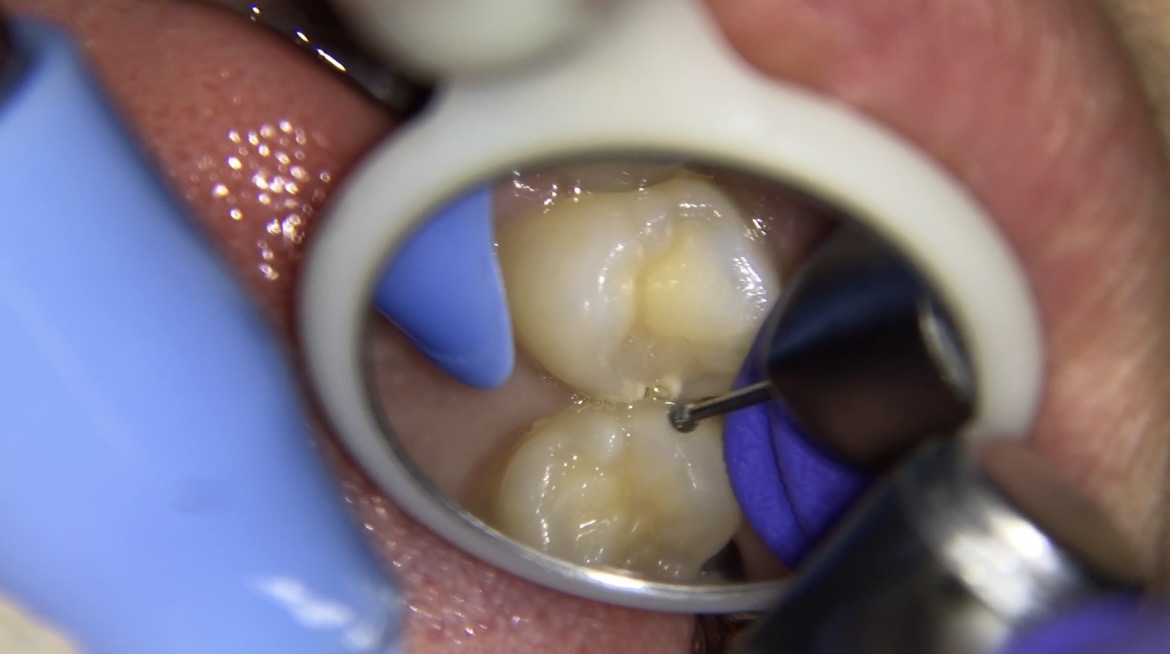

【処置前】削る前→虫歯除去

削ると歯と歯の間から虫歯が進行し、まだ虫歯が残ってる状態になります。